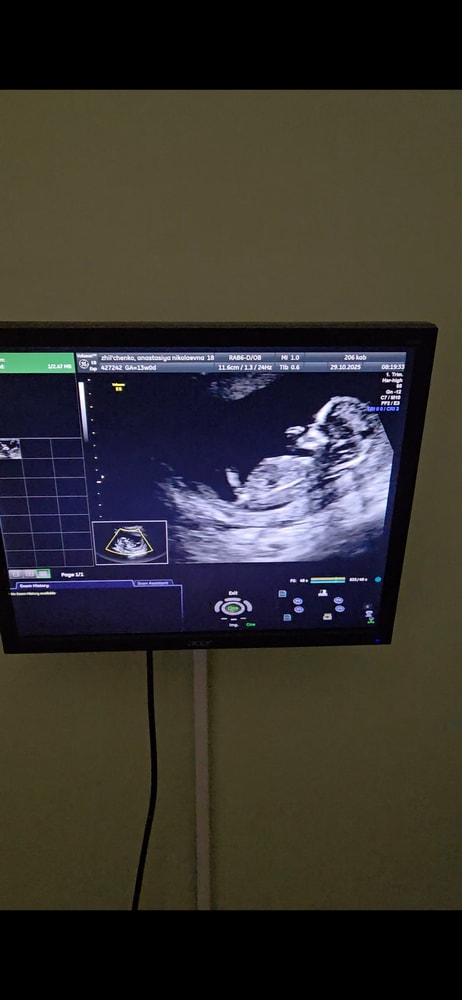

Мальчик/девочка?

Анализы, скринингиХотелось бы послушать знатоков по половым бугоркам 😄 если видно, подскажите) с видео сделала фото

Не понятно - то ли ножка, то ли бугорок. Пока похоже на мальчика.